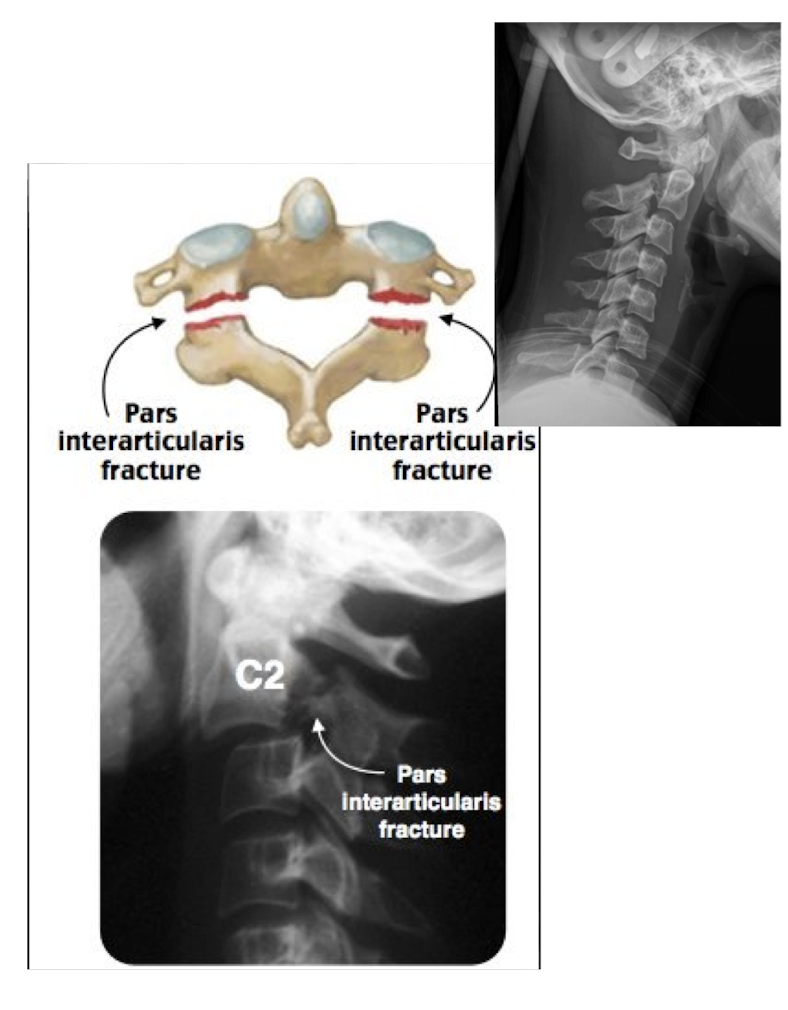

Fracture of C2: Hangman’s Fx

What type of Fx is this?

Bilateral Fx of the pedicles of C2 w dislocation of vertebral body C2 on C3

Fracture of C2: Hangman’s Fx

MOI:

__ for info on the SC

Stable or Unstable Fx

MOI:

Hyper Extension Injury in MVA

MRI

Unstable